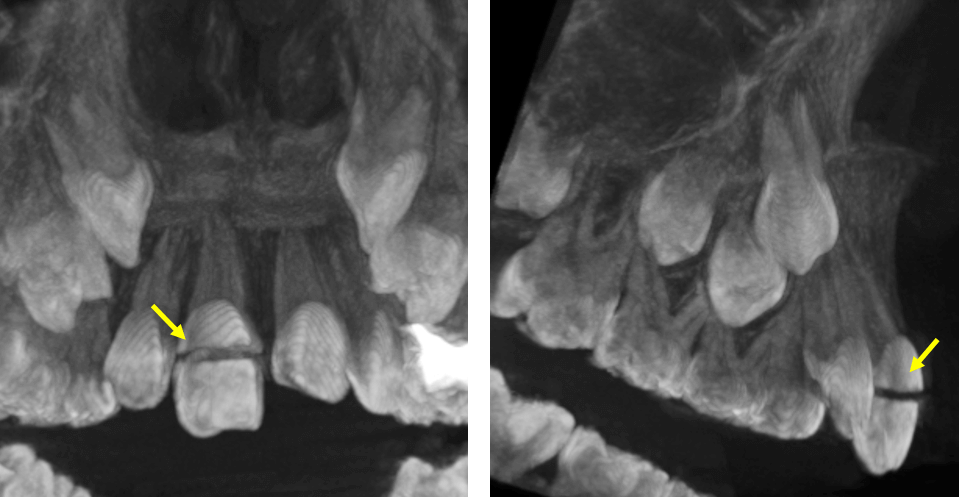

Fig.4

En la representación tridimensional (Fig.4) se observa la fractura horizontal coronaria con cierto grado de separación de segmentos.